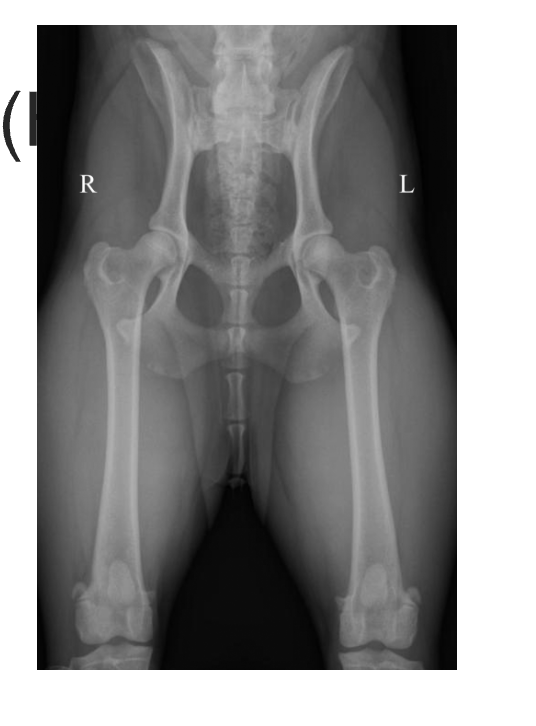

Hip dysplasia what happens

Malformation and degeneration of the coxofemoral joint

What are some of the clinical signs of HD

Can be asymptomatic at the start

May eventually observe an abnormal gait

As OA developes there is a decrease in activity, trouble rising, lameness

How to diagnoses HD

Pain elicted during palpatation/ extension of hips

Loss of muscle mass

Ortolani sign (clunk)

HD what does it look like of radiographs

Flattened femoral head

Thickened femoral neck

Shallow/ sclerotic acetabulum

Numerous osteophytes